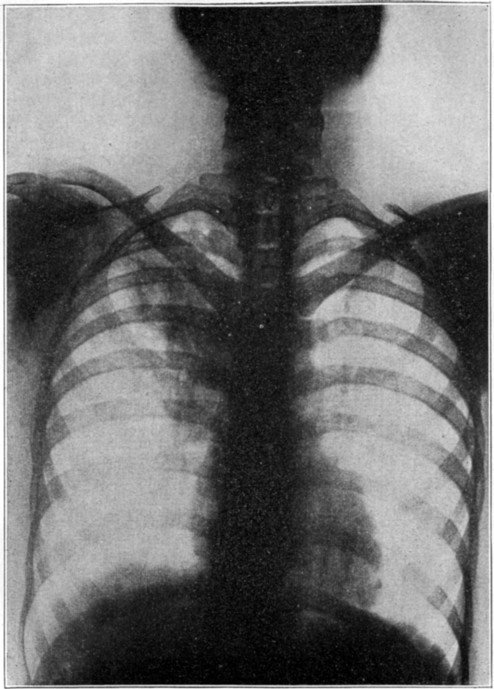

| 16 | X ray showing tuberculosis of the lung | 346 |